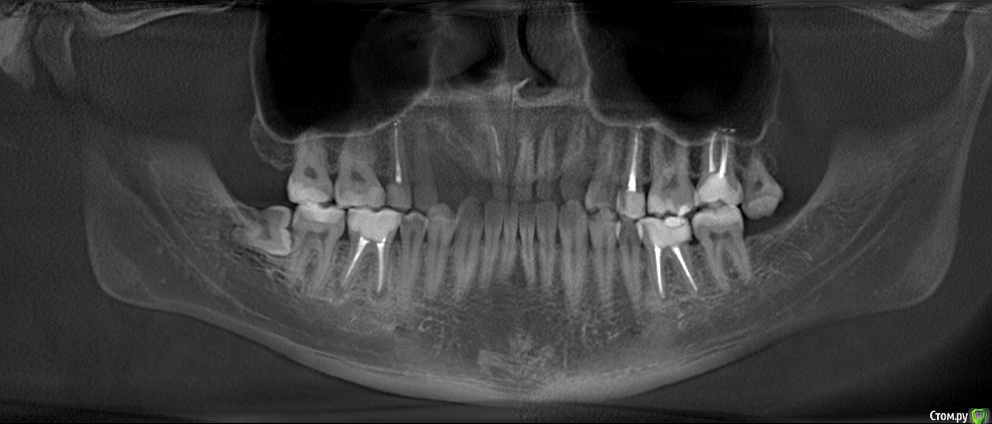

Добрый день! На протяжении нескольких лет обращался на профилактические осмоты - всегда говорили что Ок.

кто говорил, что 8ку удалять. А сходил к хирургу - сказал что все уже вырасло и раз не беспокоит - можно не трогать. Показаний нет.

В сейчас, опять сделали снимок и говорят, что на соседнем зубе кариес, причем значительный - и скорее всего нужно удалять нервы на 7ке, после удаления 8ки. Обращался по страховке.

Снимок не дали, но есть 2х летней давности. Есть ли здесь кариес или это просто тень от 8ки?

А на 47 видно следы кариеса?

Есть какая-то зона деминерализации. Лучше свежий снимок сделать.